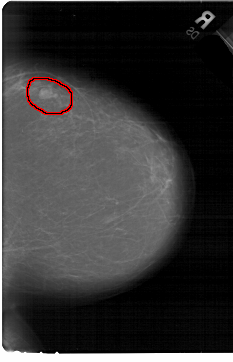

A_1440_1.RIGHT_CC

RIGHT_CC LINES 6871 PIXELS_PER_LINE 4426 BITS_PER_PIXEL 12 RESOLUTION 43.5 OVERLAY

FILE: A_1440_1.RIGHT_CC.OVERLAY

TOTAL_ABNORMALITIES 1

ABNORMALITY 1

LESION_TYPE MASS SHAPE LOBULATED MARGINS CIRCUMSCRIBED

ASSESSMENT 4

SUBTLETY 4

PATHOLOGY BENIGN

TOTAL_OUTLINES 1

BOUNDARY